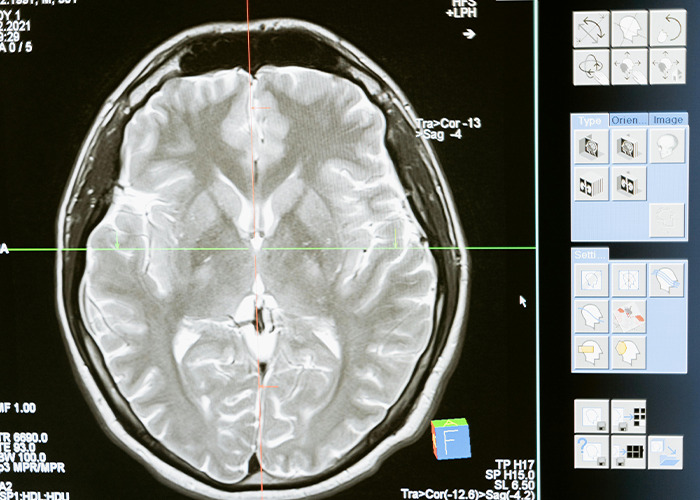

The strategy is focused on treating glioblastoma, one of the deadliest types of cancer, which is only diagnosed at stage 4 and has a five-year survival rate of around 10%.

Glioblastoma forms in the brain or spinal cord and grows quickly, invading and destroying healthy tissue. It can occur at any age but most often affects older adults, especially men, according to the Mayo Clinic.